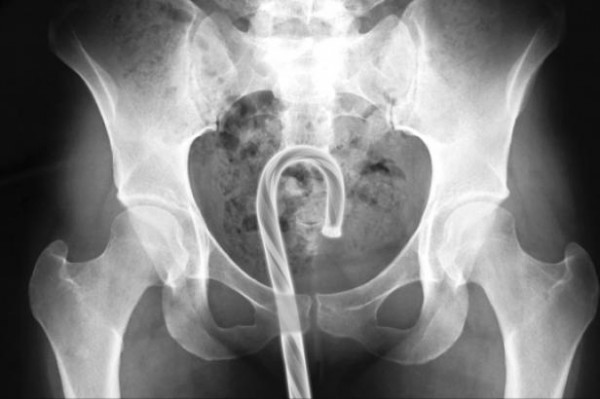

3- Les objets coincés dans...enfin vous voyez quoi !

Ouais c'est pas glorieux mais...toutes ces histoires de pompiers et d'infirmiers que vous entendez ne sont pas des légendes ! Il y a bien des gens qui arrivent aux urgences en disant qu'ils ont glissé sur une bouteille de bière qui s'est malencontreusement logée par erreur sans faire exprès sans le vouloir de façon inopinée dans leur rectum.... Mais oui mais oui allez on ne dira rien mettez vous sur le ventre !